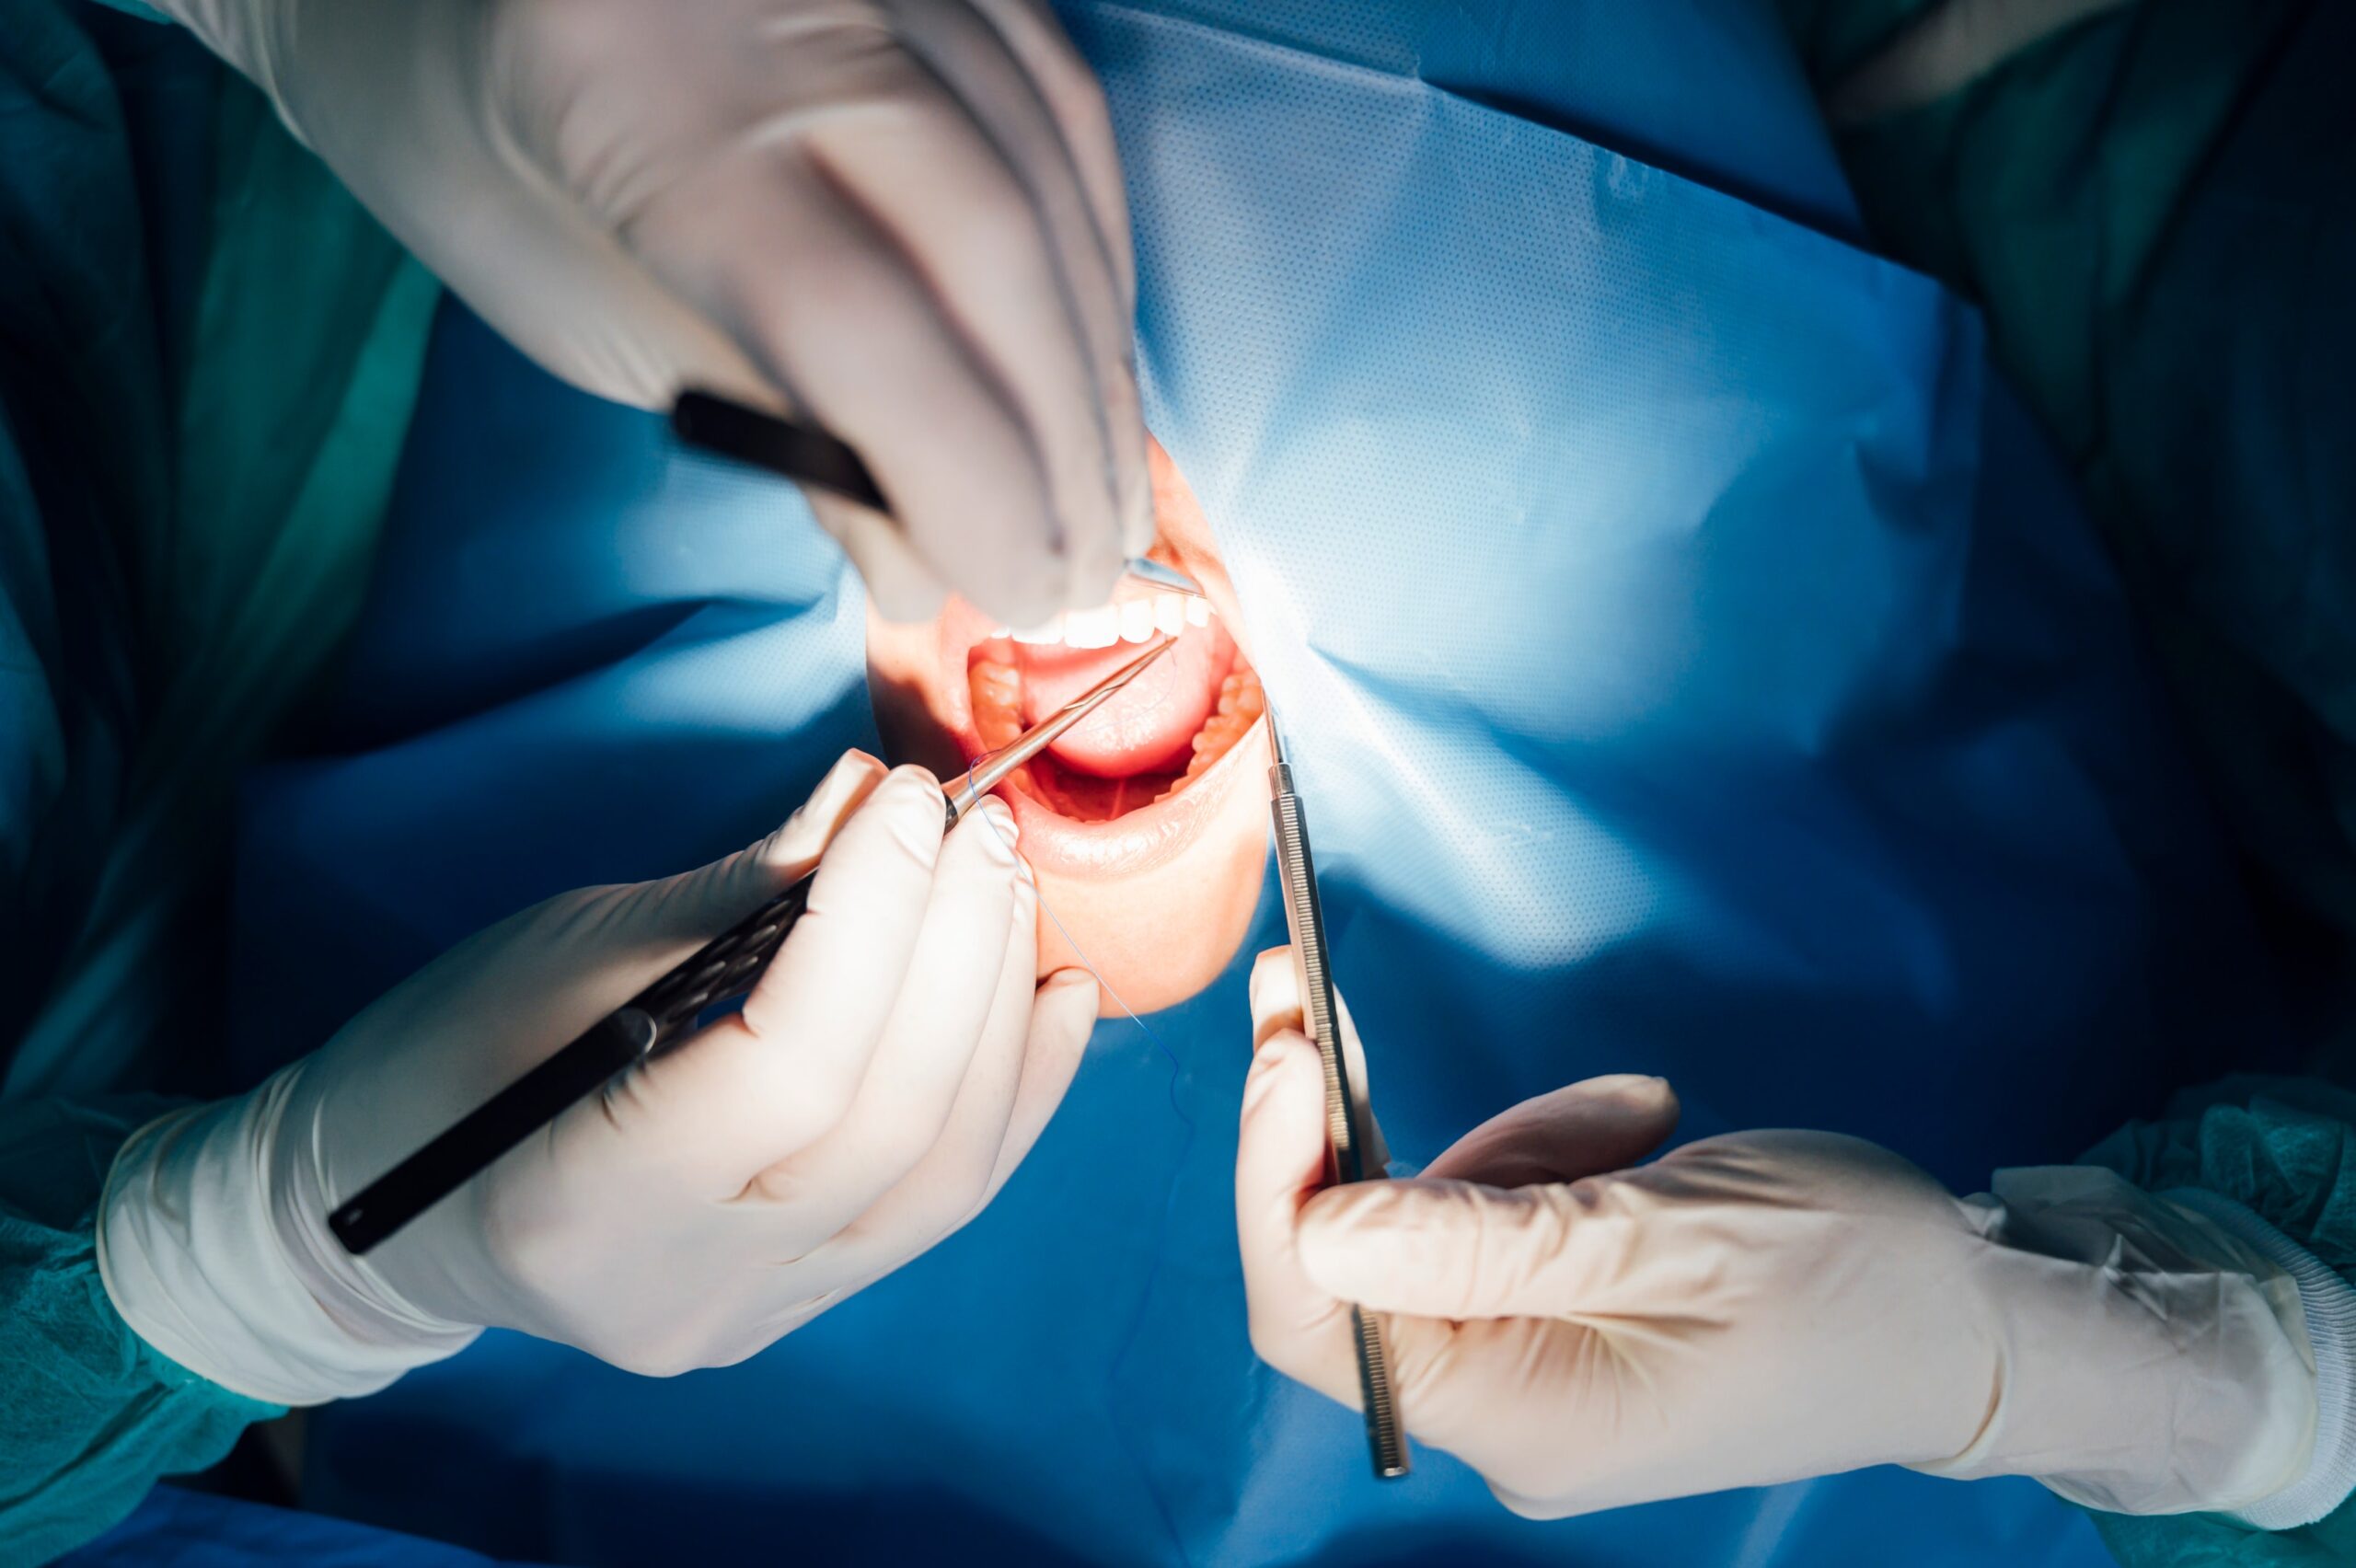

Tam Çene İmplant Tedavileri

Tam dişsizlik durumlarında, implantların dijital planlama ile çene kemiğine yerleştirilmesini içeren bir tedavi yaklaşımıdır. Üç boyutlu görüntüleme desteğiyle kişiye özel cerrahi planlama yapılabilmektedir.

İleri İmplant Tedavileri

İmplant tedavileri, eksik dişlerin tamamlanmasına yönelik uygulanan, çene kemiğine yerleştirilen titanyum yapılar üzerine planlanan bir tedavi yaklaşımıdır.

// TAM ÇENE İMPLANT REHABİLİTASYONU

Rehberli cerrahi yaklaşımı, operasyon sürecini daha kontrollü ve güvenli hale getirir.

— Full arch (tam çene) implant

Flepsiz cerrahi teknik (dikişsiz cerrahi) uygulama ile hasta konforu ve iyileşme süreci desteklenir.

— Tam dişsizlik vakaları

İmplant cerrahisi ile aynı gün uygulanan protezler, fonksiyonel ve estetik sonuçların hızlı ve güvenilir şekilde elde edilmesini sağlar.

— Kemik hacmi sınırlı vakalar